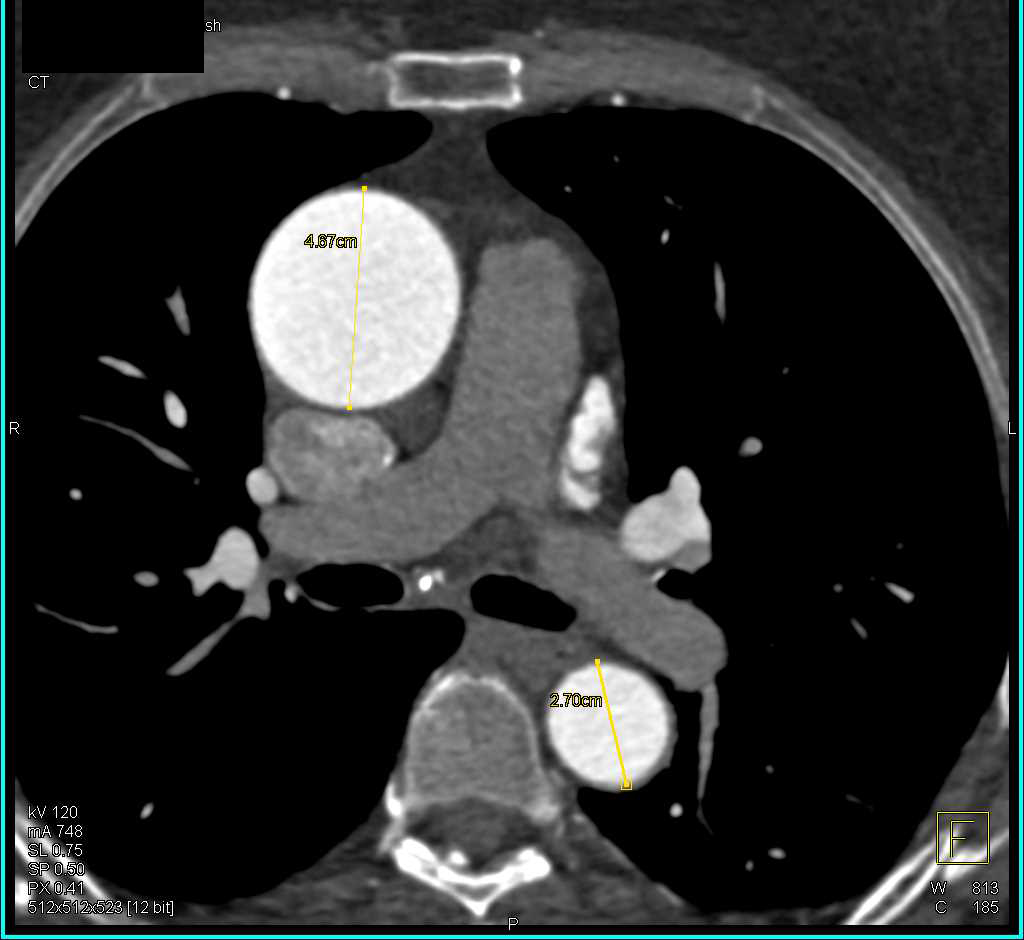

Dilated Ascending Aorta